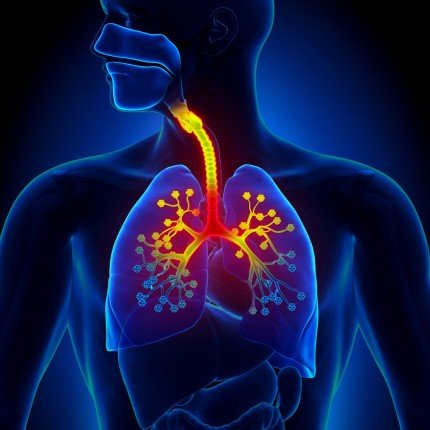

التغذية أثناء التهاب الشعب الهوائية.. الأطعمة التي يجب تجنبها لدعم صحة الرئة وتسريع التعافي

عند الإصابة بالتهاب الشعب الهوائية، قد يدفعك السعال المستمر وألم الصدر والإرهاق إلى البحث عن أطعمة سهلة التحضير ومريحة، لكن ليس كل ما هو “مريح” مفيد، فقد تزيد بعض الأطعمة من الالتهاب وتبطئ التعافي، وفقًا لتقرير موقع تايمز أوف إنديا.

يمكن للتغذية الصحيحة أثناء الإصابة بالتهاب الشعب الهوائية أن تقلل الالتهاب، تقوي المناعة، وتسهم في استعادة صحة الرئة والطاقة بشكل أسرع، بينما يمكن للخيارات الغذائية غير الصحية أن تطيل فترة المرض وتفاقم الأعراض.